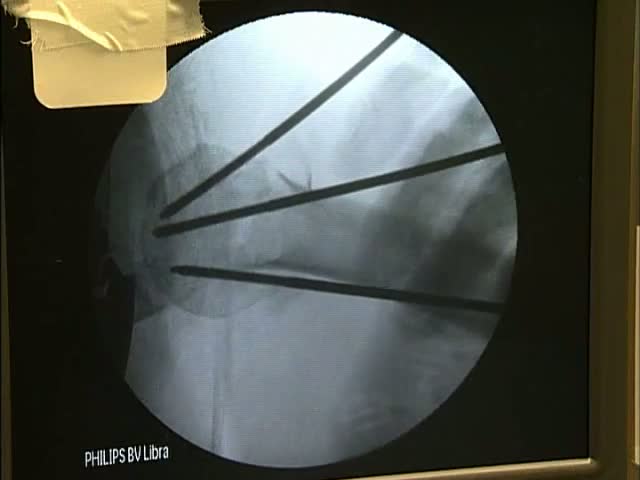

External Fixation for Proximal Humerus Fractures

Technique for reduction and fixation of 2, 3, and 4 with an external fixation device